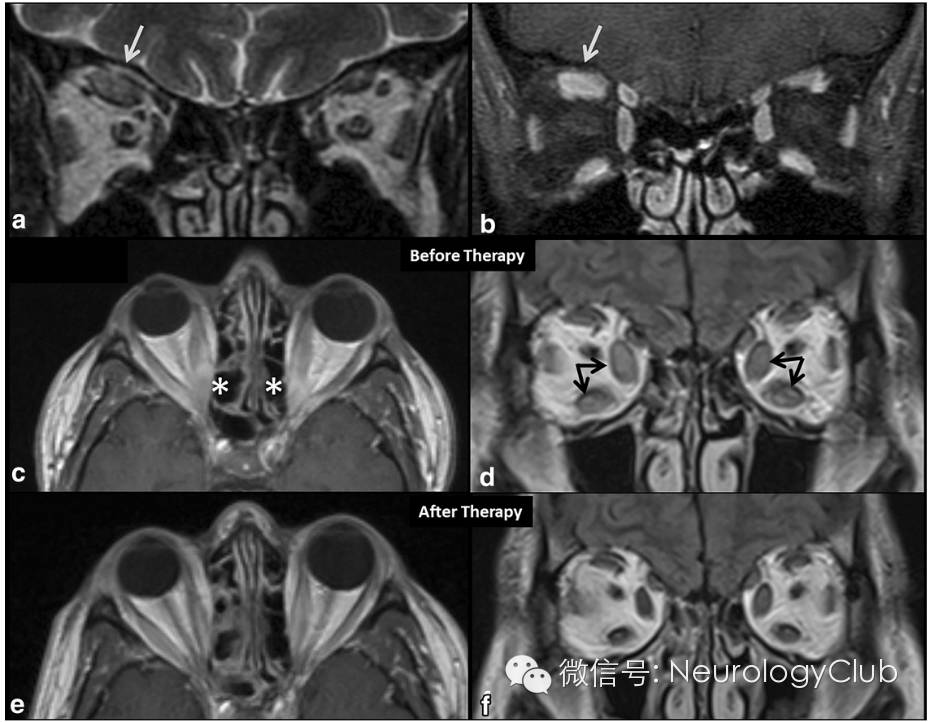

图1  眼眶肌炎的MRI表现

(a-b:局部眼外肌受累;a:右上直肌增粗,在T2WI上信号轻度增高;b:对比剂注射后可见肥大肌肉强化;c-f:多发双侧不对称眼外肌受累;c-d:内直肌和下直肌明显增粗[箭],内直肌包括肌腱附着处[*]可见T2 FLAIR高信号,右侧>左侧;e-f:激素治疗1月后明显改善,FLAIR上眼外肌直径减少,信号降低)